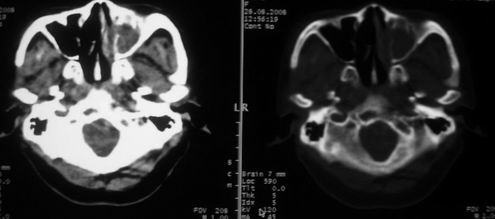

女,55岁,右侧颌下肿物3年。

右侧胸锁乳突肌后方软组织密度肿块,界限清楚。多考虑:血管源性肿瘤!

鼻咽左侧壁增厚,呈结节样突入鼻咽腔内,左侧咽隐窝消失,须考虑鼻咽癌可能,建议鼻咽纤维镜检查以明确诊断。

至于右侧颌下间隙的结节影,如果不考虑病史的话,可以诊断为淋巴结转移。但是结合病史“右侧颌下肿物3年”,又不象淋巴结转移了。建议ct增强扫描明确结节与右侧颌下腺的关系,或者穿刺活检定性。

右侧胸锁乳突肌内侧略低密度结节,应该是静内静脉而不是淋巴结。